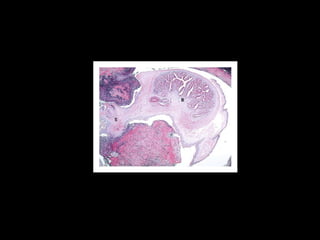

INVESTIGATIONS Stool Routine and Microscopy Fundoscopy Biopsy and histopathology CT with contrast MRI Serology EITB sensitivity of 98%  specificity of 100%   ELISA in CSF sensitivity of 87% specificity of 95%

STAGES OF NC Cystic or vesicular stage Cyst wall & scolex do not enhance  Cyst is viable & has a well defined, fluid-filled membrane contains only one scolex.  Colloid stage Enhancing walls with perilesional oedema Earliest stage in the involution of the cyst. the fluid contents of the cyst become more turbid and the scolex begins to degenerate. Necrotic, granular stage Characterized by parasite necrosis and surrounding inflammation Gives an appearance of an eosinophilic structure in which the bladder and scolex are in various stages of disintegration Oedema and/or necrosis of the surrounding neural tissue may be present in some cases Fibro-calcified nodule With time, fibrosis develops, progressively occupying the entire lesion D.Sharada et al